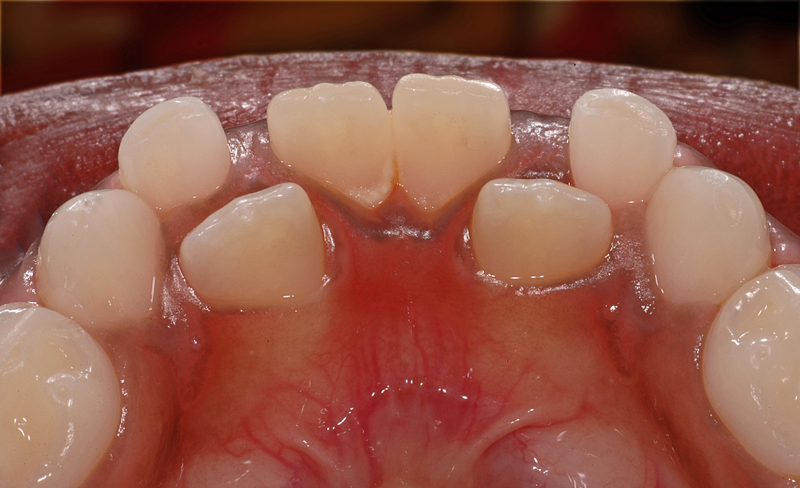

Hier ein Fall, bei dem ein oberer linker kleiner Backenzahn (ein Prämolar, Zahn 24) zu weit aussen und «oben» durchbricht. Dies ist in der Regel kein Problem, sofern der Milchzahn innert vernünftiger Frist (ein bis drei Monate) herausgewackelt werden kann; so löst sich das Problem von selbst.

Oft ist es jedoch so, dass die Milchzähne fest bleiben, weil die gaumenseitige Wurzel nicht genügend aufgelöst wird und den Zahn daher noch hält. Dann kann eine Entfernung des Milchzahnes angezeigt sein, damit sich der bleibende Zahn genügend nach innen bewegen kann und am Schluss am richtigen Platz steht und nicht zu weit aussen am unteren Zahn vorbei durchbricht.

Notfälle sind solche Situationen aber keinesfalls…